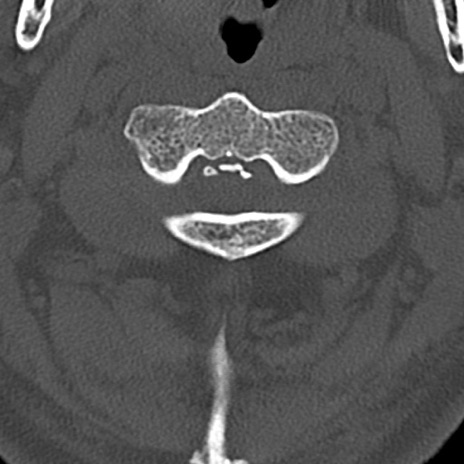

頚椎CT

横断像